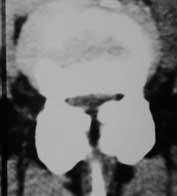

Auch hier reicht zumeist Röntgenaufnahme in Funktion sowie eine Kernspintomographie oder eine Computertomographie aus. Bei einem Wirbelgleiten oder einer Verengung auf mehreren Höhen ist eine Myelographie nach wie vor die Untersuchung, die die wertvollsten Ergebnisse im Hinblick auf eine genaue Operationsplanung liefert.